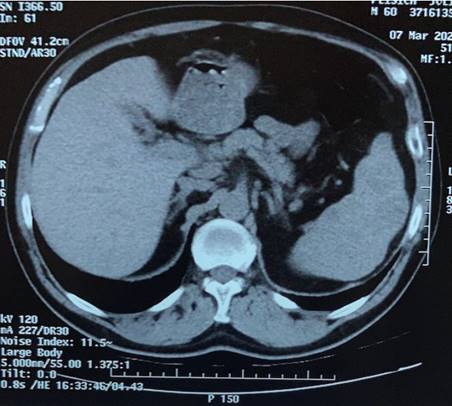

La ecografía evidencia al bazo aumentado de tamaño con múltiples nódulos. Con estos hallazgos decidimos solicitar tomografía de abdomen y pelvis con contraste intravenoso que informa: esplenomegalia leve, heterogénea, con múltiples lesiones sólidas. Hígado, páncreas y glándulas suprarrenales sanas. No presenta adenomegalias, líquido libre ni otras alteraciones (figura 1).

Figura 1: Tomografía de abdomen y pelvis. Corte axial. Esplenomegalia. Bazo con nódulos sólidos.